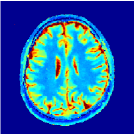

Two sets of experiments were conducted here: first, we used the 2D and 3D acquisition sequences for scanning a healthy volunteer’s brain (real-world acquisitions). Figures 6 and 7 display the parametric maps reconstructed from 2D spiral and radial readouts. We computed the T1, T2 and proton density (PD) maps using baseline reconstruction algorithms ZF, VS, LR, FLOR, AIR-MRF and our proposed LRTV. While baselines use DM either for quantitative inference or also during reconstruction (i.e. AIR-MRF), we further compare the DM-free LRTV’s performance when cascaded to DM, KM and MRFResnet for quantitative inference. For the 3D spiral acquisitions we compared LRTV and its closest competitor VS in Figure 8. Outcomes from other tested algorithm are displayed in the supplementary materials (Figure S5). Since FLOR does not use dimensionality-reduction, our system ran out of memory during 3D reconstruction; hence results are not reported in this case.

The LRTV-DM and LRTV-MRFResnet perform on par, and both outperform all tested baselines for reconstructing T1, T2 and PD maps in all acquisition schemes. This can be observed both visually in Figures 6, 7, 8, S2 and S3, and quantitatively in Table IV across all tested metrics. Other baselines were unable to successfully remove the under-sampling artefacts in TSMIs, and these errors propagated to the parameter inference phase and resulted in inaccurate maps. Temporal-only priors incorporated within LR are shown insufficient to regularise the inverse problem and LR sometimes (e.g. 2D spiral acquisitions) can admit solutions with even stronger artefacts than the model-free ZF baseline. This issue was previously studied for other non-Cartesian MRF readouts that similar to our spiral/radial trajectories, miss to sample the corners of the k-space in all timeframes (see section 2.2.2 and figure 2 in [19]). In the absence of reference for the k-space corners information, the LR iterations despite minimising the objective can converge to solutions with high-frequency artefacts, as visible in the computed maps. This highlights the need for adding an appropriate spatial-domain regularisation. FLOR reduces the LR’s artefacts but this improvement is limited because the suggested nuclear norm penalty does not incorporate an explicit spatial regularisation. Further for reducing artefacts, FLOR can introduce an undesirable bias in the computed T1/T2 maps e.g. see error maps in Figures S2 and S3. The non model-based VS baseline incorporates spatial regularisation and results in spatially smoother maps than ZF and LR, but it is unable to output artefact-free images. Further and consistent with our in-vitro experiment, we observe that VS overestimates the T2 values (e.g. in White and Grey matter regions) in tested 2D acquisitions i.e. the spatial regularisation trades off agains the quantification accuracy. The model-based AIR-MRF adds spatial regularisation through 2D/3D low-pass Gaussian filters however this trades off the sharpness of the computed maps and can increase the errors at the tissue boundaries (we searched Gaussian spreads that keep the blurs and high-frequency artefacts minimal). For our acquisition readouts, Gaussian filters performed better than disk filters of [19] for avoiding strong Gibbs artefacts. On the other hand, the spatiotemporally regularised LRTV greatly improves the TSMI reconstructions i.e. 4 dB enhancement compared to the closest competitor baseline (Table IV). This enables computing accurate and aliased-free multi-parametric inference using DM or the DM-free learning-based alternative MRFResnet as visible in Figures 6, 7, 8, S2 and S3. MRResnet and DM score competitive quantitative inference results i.e. T1 and T2 MAPE less than 5% and 9%, respectively (Table IV). KM also outputs comparably accurate T1 maps, however this shallow learning model despite having a model size larger than MRFResnet, is unable to learn accurate T2/PD quantification and it results in poor estimated maps, consistent with our observations in section VI-C.